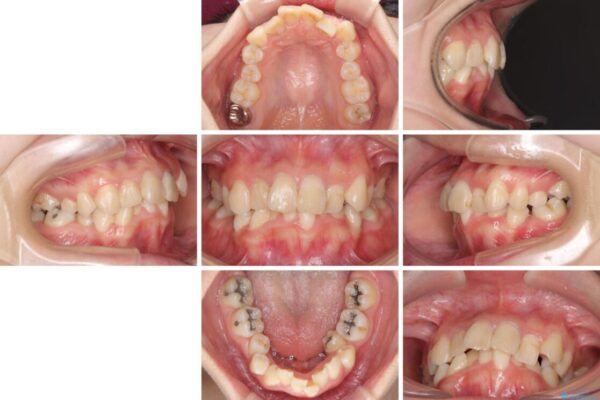

内側に倒れ込んだ歯や下の前歯が隠れてしまうほどの咬み合わせを改善したいとのことで来院された患者様です。

下顎の叢生を解消するために抜歯が必要であり、奥歯の咬み合わせや口元の印象から、上顎も同様に抜歯と判断し、上下左右の第1小臼歯4本抜歯してワイヤー装置にて矯正治療を行うこととしました。

咬み合わせが深く、そのままでは上顎の抜歯スペースが閉じきらない可能性があったため、治療初期から深い咬み合わせを改善させるように試みました。

実際にはなかなか改善されず、当初予定よりも治療期間がやや長期化してしまいました。

治療前

治療途中

• デコボコと深い咬み合わせ ワイヤー装置での抜歯矯正 治療途中画像